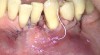

Fig 13. The scaffold was placed in the defect, where it remained for approximately 1 year. Fig 13: baseline; Fig 14: defect; Fig 15: scaffold matrix; Fig 16: scaffold placement; Fig 17: wound closure; Fig 18 through Fig 20: 2-month, 6-month, and 1-year postoperative, respectively. (Images reprinted with permission from Rasperini G, Pilipchuk SP, Flanagan CL, et al. J Dent Res. 2015;94[9 suppl]:153S-157S.)

Figure 13